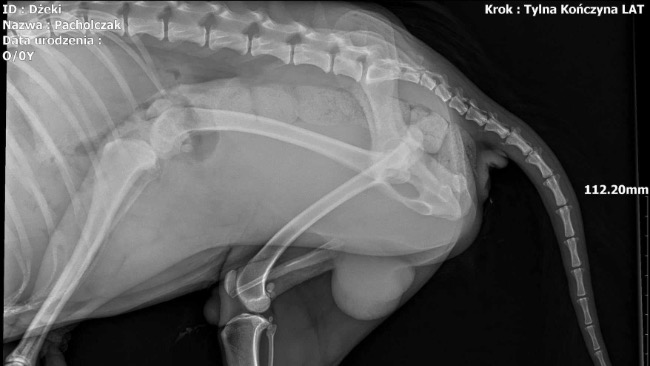

Dnia 24.11 wykonano badanie RTG z powodu kulawizny prawej tylnej kończyny.

Na zdjęciach stwierdzono wystawienie główki kości udowej prawej z panewki stawu biodrowego. Zalecono zabieg resekcji (usunięcia) główki kości udowej w celu wytworzenia stawu rzekomego.